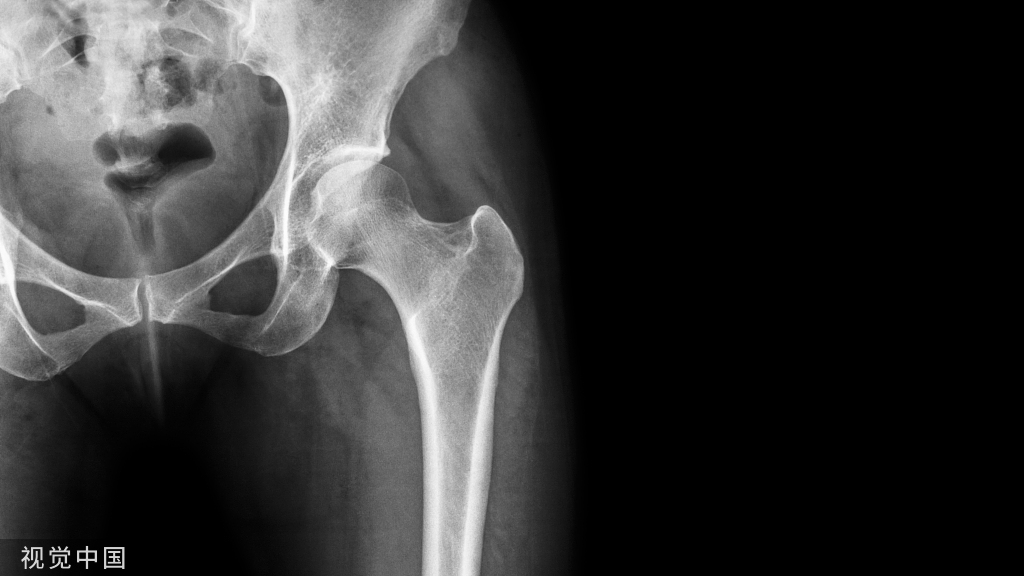

外科手术的目的是为了获得解剂复位,并在骨折愈合前以内固定的方式来维持复位状态,恢复髌骨骨折后的伸肌装置(图5)。

前张力带可将股四头肌产生的牵拉力转化为对关节面的压力。

图5